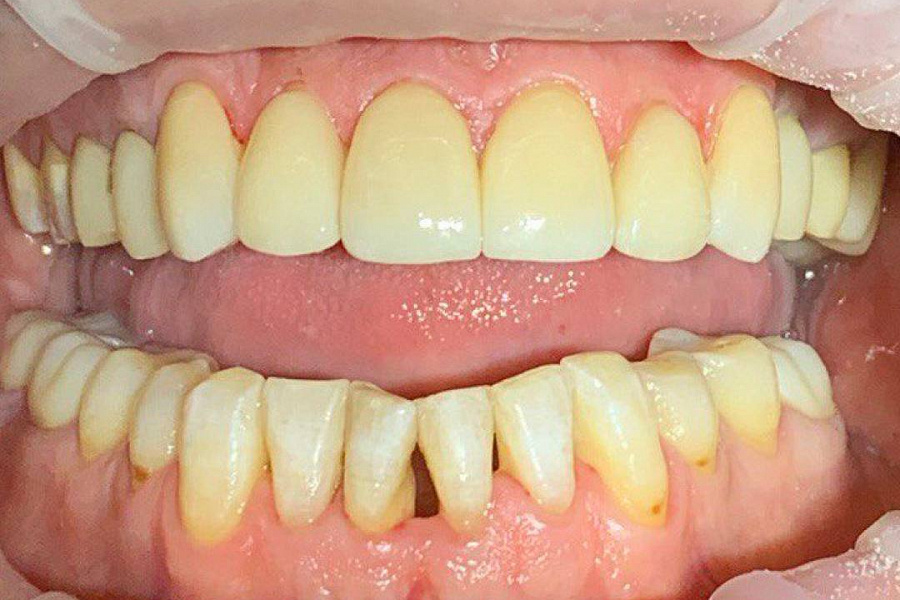

Была проведена сложная междисциплинарная работа:

1. Восстановлена правильная позиция зубов с помощью ортодонтического лечения под наблюдением гнатолога, но в связи с высокой стираемостью этого было недостаточно.

2. Была проведена ортопедическая реабилитация ортопедическими конструкциями с восстановлением высоты нижней трети лица и формы стертых зубов.

В результате мы получили сохранность ситуации , которая не ухудшается дальше. Лицо стало более молодым и подтянутым. Пациент перестал скрипеть зубами и стирать свои собственные зубы.